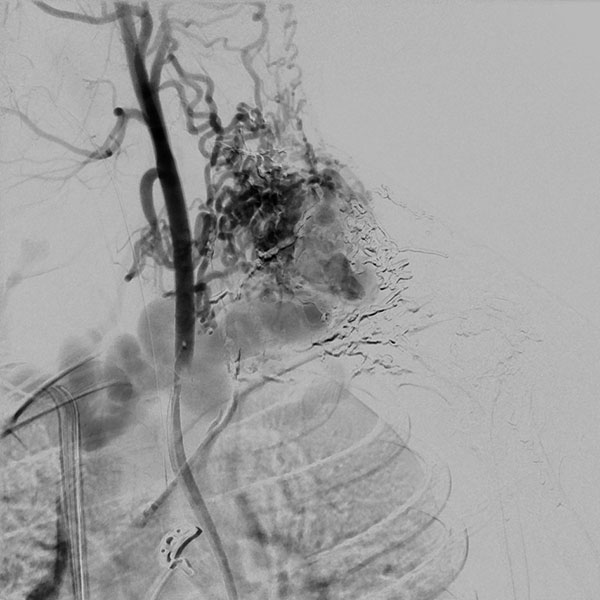

Digitale Subtraktionsangiographie (DSA), Nativbild. Der Nidus der arteriovenösen Malformation wurde jetzt in 2 Sitzungen sukzessive nach direkter Punktion mit einer Nadel mit dem flüssigen, zäh wie Lava fließenden Embolisat Ethylen-Vinyl-Alkohol-Kopolymer (EVOH) aufgefüllt im Sinne einer Embolisation. Der Nidus ist am Ende nach Injektion von 37 Ampullen des röntgendichten Embolisats komplett aufgefüllt. Es kommt zu keinem Durchstrom mehr, die arteriovenöse Malformation ist verschlossen.

Digitale Subtraktionsangiographie (DSA) mit proximaler Injektion in die linke A. subklavia mit Darstellung der A. vertebralis nach Abschluss der 2. Embolisation. In dieser späten Phase nach Injektion stellen sich zwar noch einige arterielle Feeder dar, diese finden jedoch keinen Anschluss mehr an den Nidus der arteriovenösen Malformation. Auch zeigt sich kein venöser Abstrom mehr. Damit ist die AVM verschlossen.